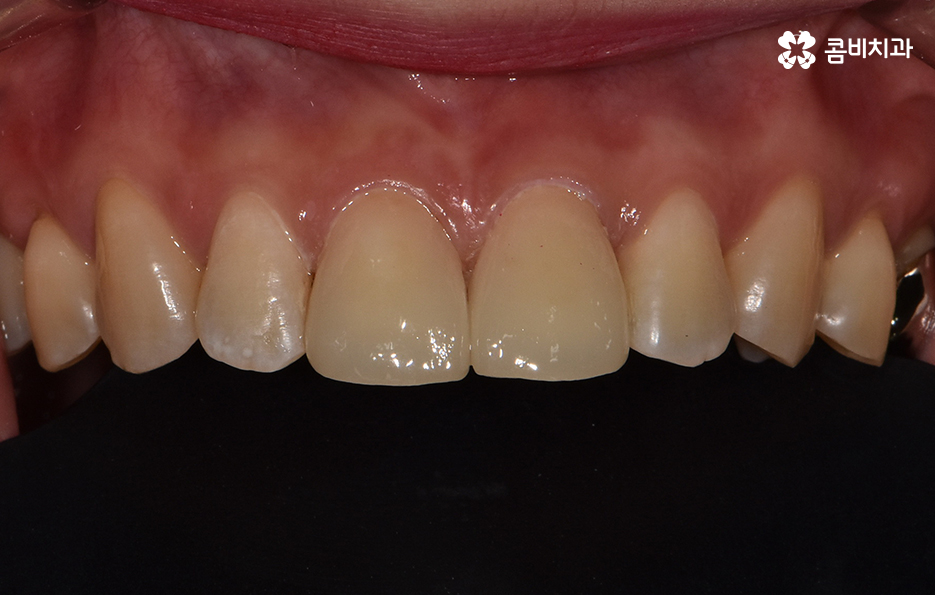

위 환자분의 경우 블랙트라이앵글 레진으로 치료를 하였는데

이러한 레진 치료의 장점은 빠르게 심미성을

회복할 수 있다는 점이며 비교적 저렴하다는 장점이 있습니다.

앞니 사이의 벌어짐을 라미네이트를 통해 치료한 케이스

블랙트라이앵글은 레진을 통해서 치료도 가능하지만

레진은 간단한 반면에 떨어지거나 변색이 발생할 수 있으며

잇몸 염증을 유발하게 되는 경우도 있습니다.

보다 심미적인 치료를 위해서 치간 삭제를 통해서

라미네이트나 올세라믹과 같은 치료 방법이 활용되기도 합니다.

라미네이트의 경우 심미적으로 우수한 효과를

빠르게 낸다는 장점과 함께 치아 삭제에

대한 부담이 다소 있을 수 있습니다.